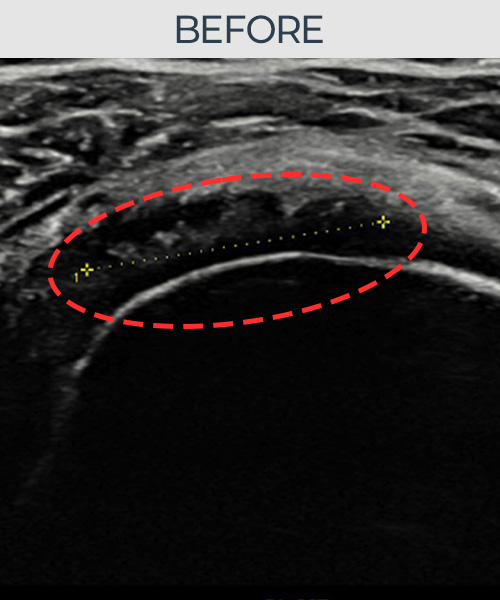

비수술 치료 전후사진

인대강화 주사가 아닌

인대재생 주사!

비수술로도 파열된 인대를

물리적으로 재건해 드립니다

플래티넘정형외과에서는 수술없이도 물리적으로

파열된 인대를 재건

하는것이 가능합니다.